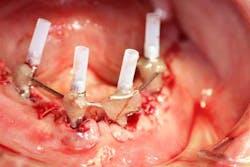

Surgery commenced. Implants on the lower arch were placed first (figures 7 and 8) and then we switched to the maxillary. The teeth were removed (figures 9 and 10) and the ridge was evened out (figures 11-13). The implants were aligned with the denture (figure 14) and then placed accordingly (figures 15-17). Healing caps were put on, and we were ready to start the restorative phase (figures 18-19).